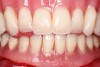

The patient presented with an edentulous maxillary arch. The mid-palatal lesion was caused by an ill-fitting denture. Pathology was ruled out by

biopsy.

Fig 1